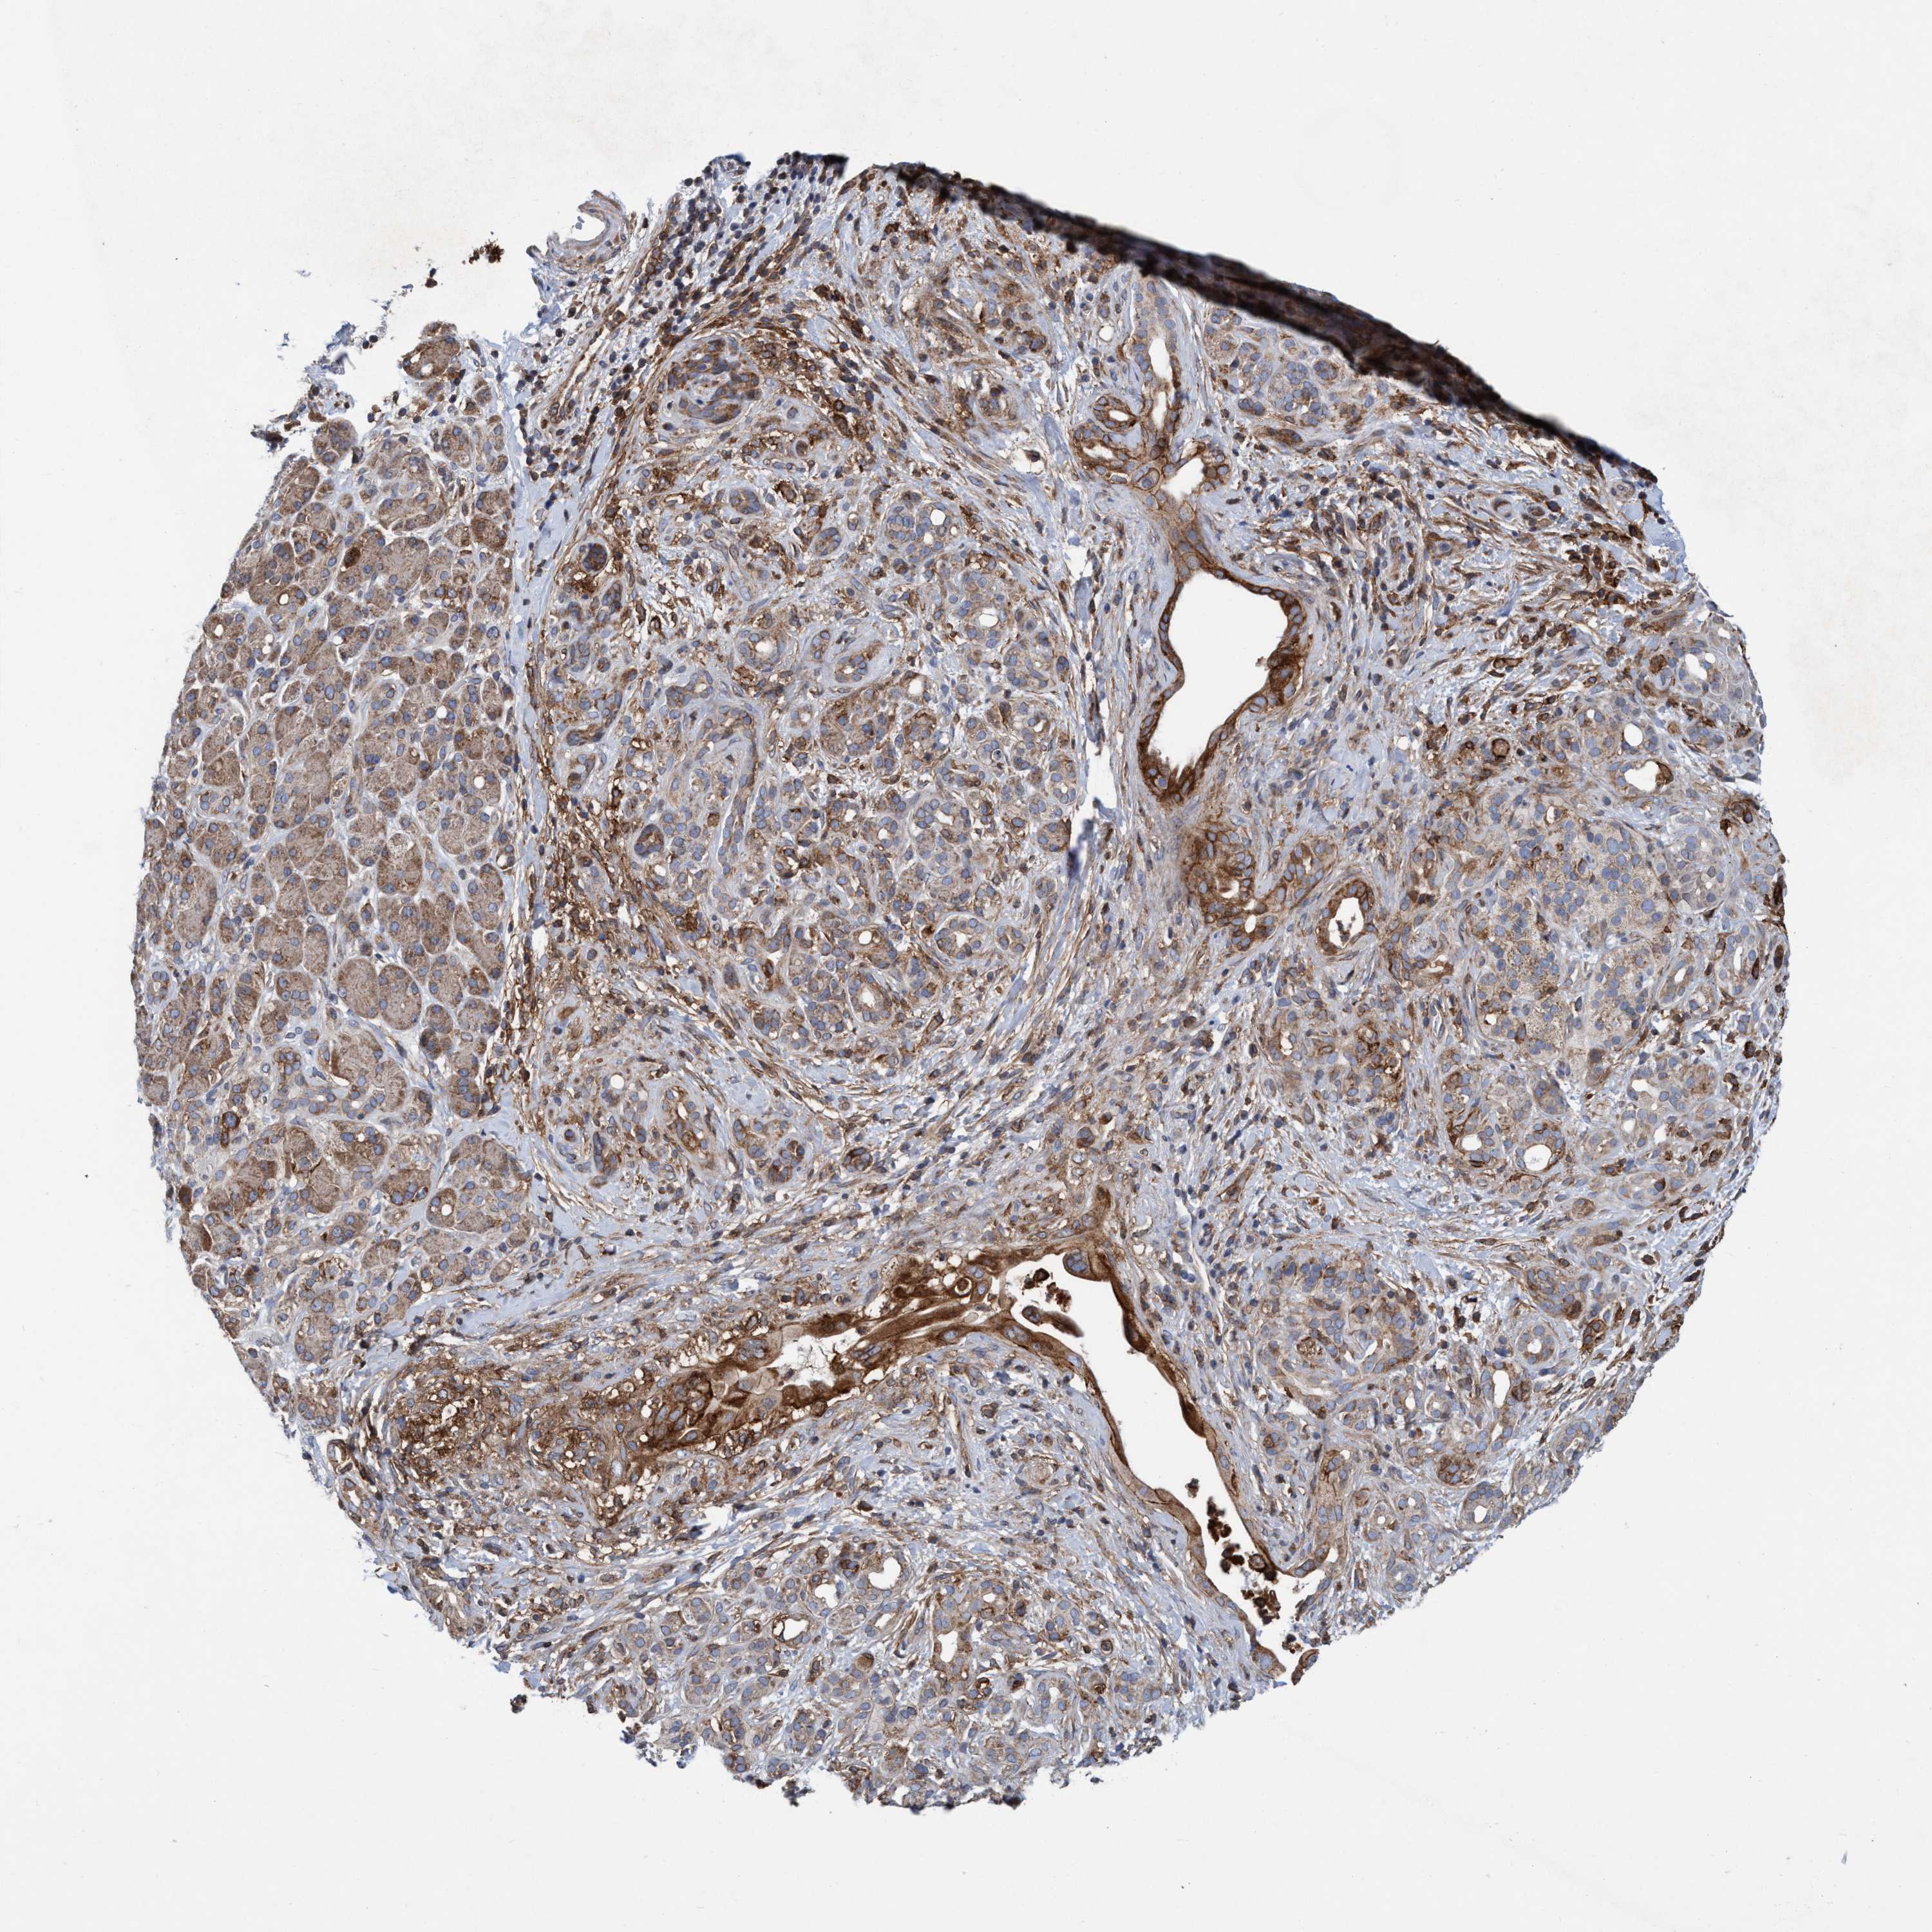

PANCREATIC CANCER - Protein expressioni

A mouse-over function shows sample information and annotation data. Click on an image to view it in a full screen mode. Samples can be filtered based on level of antibody staining by selecting one or several of the following categories: high, medium, low and not detected. The assay and annotation is described here.

Note that samples used for immunohistochemistry by the Human Protein Atlas do not correspond to samples in the TCGA dataset.

Antibody stainingi

Antibody staining in the annotated cell types in the current human tissue is reported as not detected, low, medium, or high, based on conventional immunohistochemistry profiling in selected tissues. This score is based on the combination of the staining intensity and fraction of stained cells.

Each image is clickable and will lead to virtual microscopy that enables deeper exploration of all samples and also displays staining intensity scores, fraction scores and subcellular localization as well as patient and tissue information for each sample.

Antibody HPA021451

Antibody CAB017490

Staining

High

Medium

Low

Not detected

Intensity

Strong

Moderate

Weak

Negative

Quantity

>75%

75%-25%

<25%

None

Location

Nuclear

Cytoplasmic/membranous

Cytoplasmic/membranous,nuclear

Adenocarcinoma, NOS